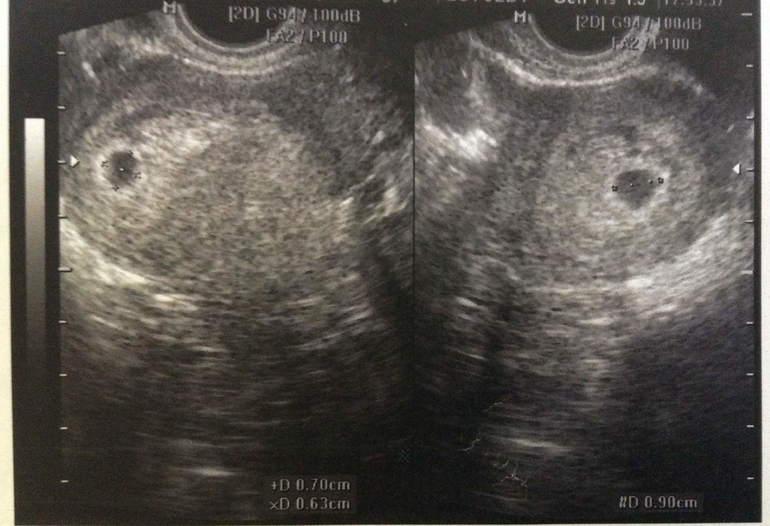

Вопросы про УЗИ, обследования и анализы: что, где, как, когда?Привет! Вчера делала первое узи. Узистка сказала что все в норме, срок примерно 5 недель и 1 день (так оно и есть по дате месячных), я начала задавать ей кучу вопросов:

Почему не видно биение сердечка? Она сказала, что пока рано и не виден эмбриокомплекс и соответственно сердечко не прослушивается. Надо сделать повтор через 10 дней. Сказала, что это нормально.

Вот какие результаты:

Читаю в интернетах, что в 5-6 уже должно биться сердечко и быть видны какие-то очертания. (( надеюсь конечно что и правда все нормально, но никак не могу бороться со своей паникой и боязнью ЗБ (хотя вот нет никакой предрасположенности, кроме чтения дурацкого интернета).